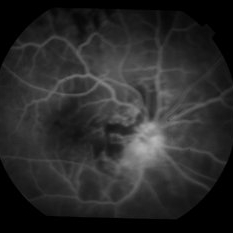

Late phase fluorescein angiogram of an eye with radiation optic neuropathy and maculopathy shows optic disc and macular hyperfluorescence. She was treated with systemic steroids for the optic neuropathy and intravitreal avastin and macular grid laser for the maculopathy with marked visual improvement.